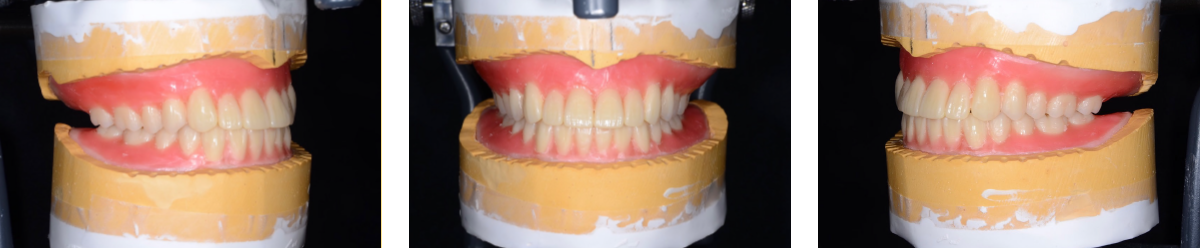

人工歯排列

入れ歯の歯を並べる過程の写真です。即時義歯ではパーツごとに模型の歯を削って、そこに人工歯を並べることを繰り返していきます。 歯を抜いた後の歯ぐきの形を想像しながらの作業は精密な診査と経験が必要になります。